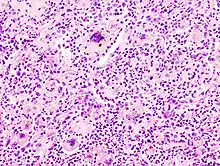

- Histologisch: Nekrosen, Kapillarisierung (Neoangiogenese), Aufhebung der normalen Histologie.

- Zytologisch: Polymorphie, basophiles Cytoplasma, erhöhte Kern/Plasmarelation

- Nukleär: Polymorphie, Polychromasie, Hyperchromasie, Aneuploidie, (vergrößerte) Nukleolen, vermehrt Mitosen, atypische Mitosen, erhöhter Proliferationsindex (Ki-67 = MIB-1).